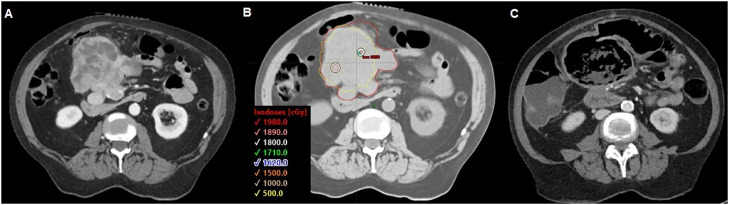

Median GTV volume for SFRT was 636 cc (range, 47-13,373 cc; IQR, 1975 cc). Two patients did not have a GTV volume for SFRT contoured. In addition, 20 Gy was the most used SFRT dose (n = 48, 79%; range, 16-20 Gy). Most courses were treated with a VMAT lattice technique (n = 52, 85%). Brass and proton GRID were used in 6 (10%) and 3 (5%) courses, respectively. Figure 1 shows representative brass, VMAT, and proton SFRT plans from the cohort.

Figure 1.

(A) Brass spatially fractionated radiation therapy plan for 26-year-old woman with malignant phyllodes of the chest-wall. (B) volumetric modulated arc therapy lattice plan 55-year-old woman with abdominal gastrointestinal stromal tumor (GIST). (C) Proton spatially fractionated radiation therapy plan for 56-year-old woman with pelvic osteosarcoma. All plans were treated to 20 Gy.